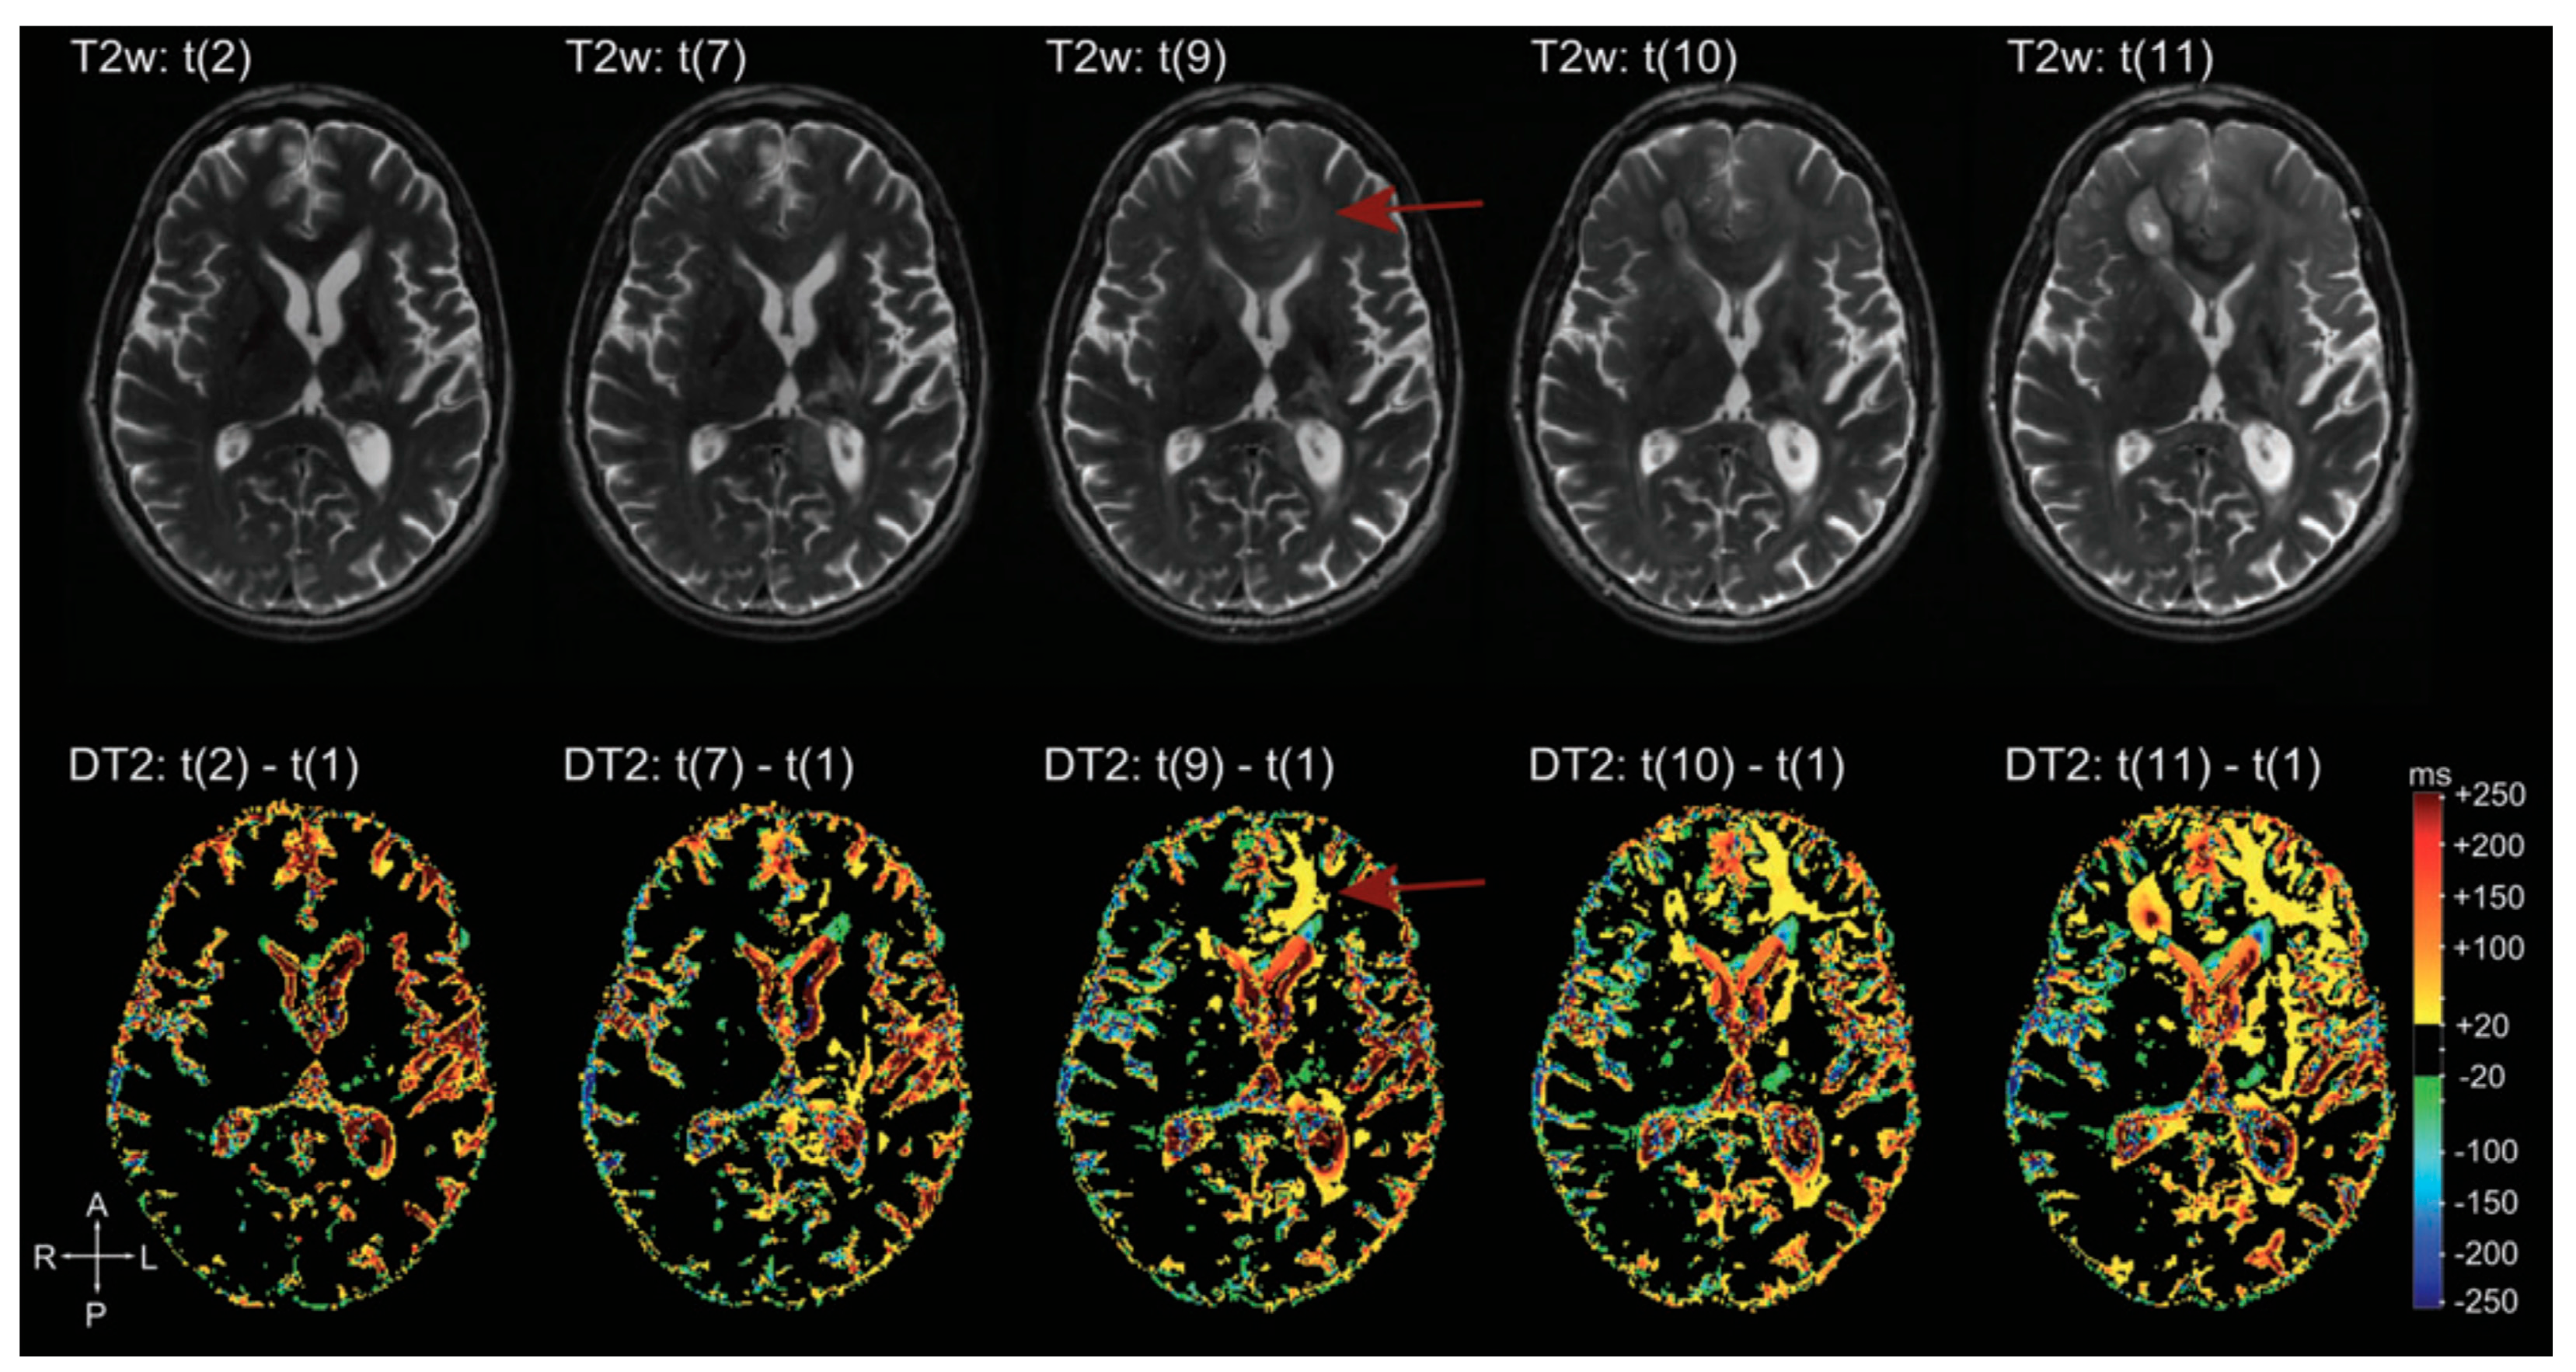

There are many applications of qMRI in the evaluation of brain tumors. First, it is used to detect tumor infiltration beyond the enhancing part of HGG, according to the fact that recurrence often arises from resection margins, suggesting that this area represents a non-enhancing infiltration zone. qT1 difference maps (post-contrast T1w—pre-contrast T1w) show moderate GBCA accumulation in peritumoral edema, and in some cases even beyond, not evident in conventional images, signs of subtle BBB leakage, and therefore tumor infiltration [163,164]. Secondly, it allows neuropathological characterization of brain microstructure. In general, BTs show increased T1 and T2 relaxation times. T1, T2, T2* relaxation times are correlated with lactate dehydrogenase, inversely correlated with vessel density; the relative difference between T1 relaxation times pre-to-post GBCA shows a weak correlation with Ki67 and a negative correlation with the amount of necrosis [165]. Third, it is helpful to distinguish between recurrence and post-treatment changes during follow-up. Many studies evaluated patients under anti-angiogenic therapy (e.g., Bevacizumab) and demonstrated that “longitudinal” subtraction maps (particularly post-contrast T1) lead to an earlier detection of recurrence than conventional MRI (Figure 17). Moreover, qMRI aids prediction of OS and PFS: Ellingson et al. suggested that patients with a post Bevacizumab T2 relaxation time higher than 160 ms would progress earlier (both OS and PFS were statistically significant) [166]; Ellingson et al. demonstrated also that post-contrast T1 subtraction maps allow for the prediction of OS and PFS from the decreasing tumor volume after Bevacizumab, with a direct correlation between decreasing volume and OS and PFS (data not showed from conventional MRI) [167].

Figure 17.

Example of T2 subtraction maps at different time points during follow-up. Upper row: T2 images at different time points. Lower row: T2 subtraction maps (with reference to time point one, not showed) at the same time points. T2 subtraction maps sharpen the evolution of T2 signal during time, hardly visible at the beginning on conventional T2 images (difference more evident at time point 9, red arrow) [168].